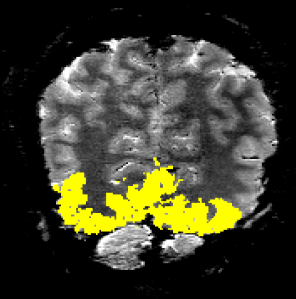

Orientation decoding accuracy across layers. (Data from Insub Kim) corresponding ROI: